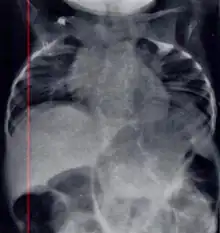

| Radiograph depicting typical skeletal features of Jarcho-Levin syndrome, subtype spondylothoracic dysplasia. Note fanlike configuration of the ribs, with extensive posterior fusion, along with multiple vertebral segmentation defects. | |

Spondylothoracic dysplasia, or STD, has been repeatedly described as an autosomal recessively inherited condition that results in a characteristic fan-like configuration of the ribs with minimal intrinsic rib anomalies. Infants born with this condition typically died early in life due to recurrent respiratory infections and pneumonia due to their restricted thorax.[3][4][5] Recently, a report[6] has documented that actual mortality associated with STD is only about 50%, with many survivors leading healthy, independent lives.